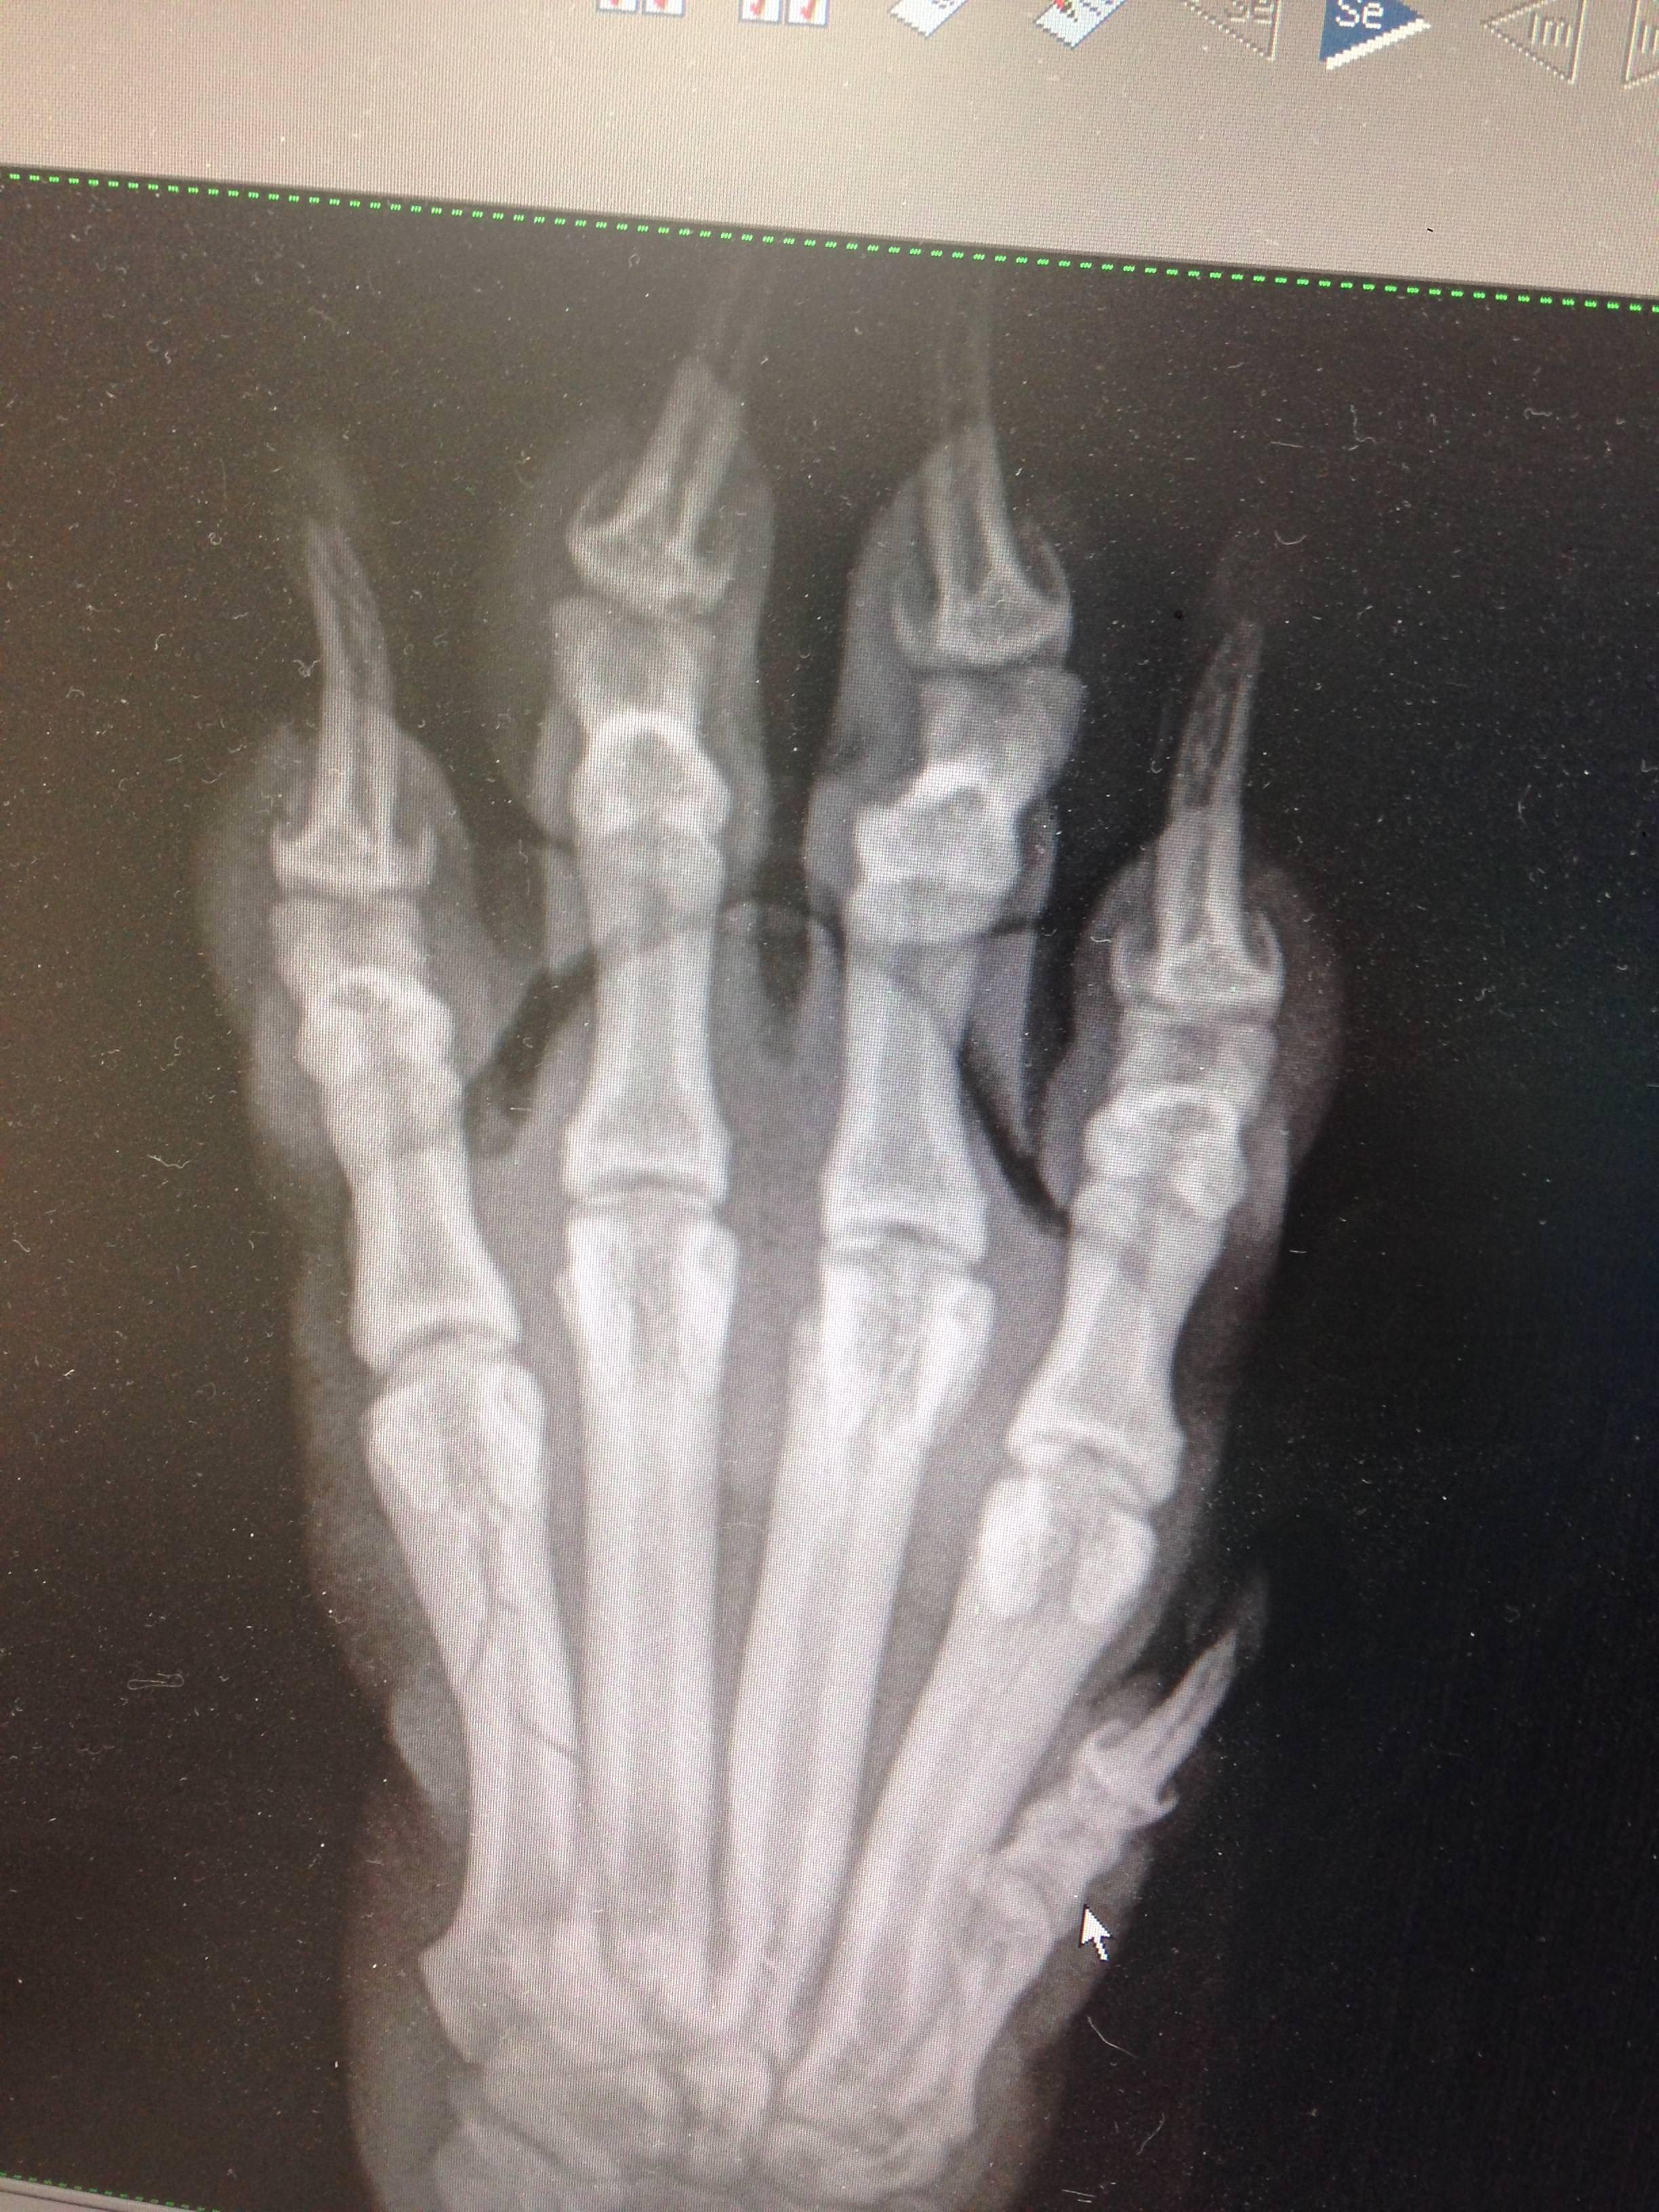

Will my Dog walk normal again? I have a 26-27 pound terrier mix. He accidentally broke his toe (we don't know how it happened). He has splint (?) bandages on his leg. My ONLY concern is will he walk normal again when the bone is fully healed? I've heard so many horror stories when a dog breaks their bones/legs, they're unable to walk normal again (limping). x ray photos attached. From what I understand the broken bone only occurred in his last (first?) toe. Thank you

Yes he should make a full recovery from that injury. It is not a weight bearing surface since it has the other toes to help. Once a callus is formed and the splint is able to come off, then he will limp while he gets range of motion back in the foot, then will walk normal